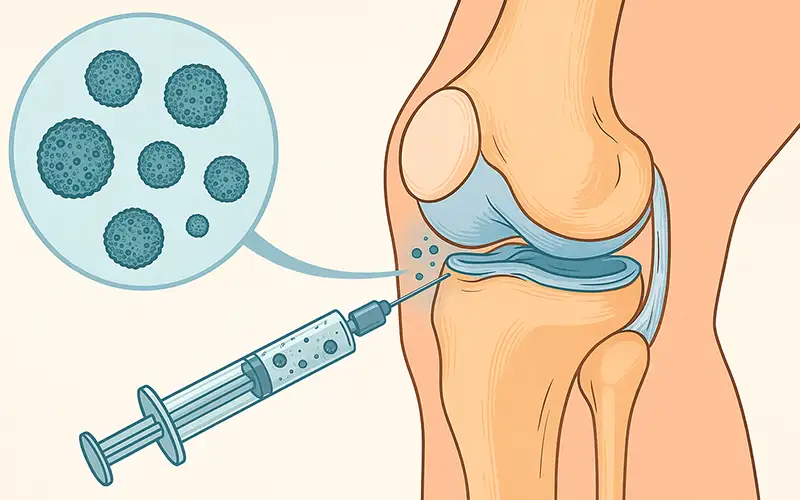

در روش اگزوزوم تراپی، این ذرات پس از فرآوری، به صورت محلول آماده به داخل مفصل یا بافت مورد نظر تزریق میشوند. هدف از این تزریق، تقویت فرآیندهای طبیعی بدن برای ترمیم، کاهش التهاب و حمایت از سلولهای آسیبدیده است. این پیامرسانهای کوچک میتوانند باعث فعالسازی مکانیسمهای درونی ترمیمی در بافتها شوند و به همین دلیل در درمان مشکلات اسکلتیعضلانی توجه زیادی را به خود جلب کردهاند.

اگزوزومها عمدتاً از سلولهای بنیادی مزانشیمی (MSC) یا منابع زیستی مشابه استخراج میشوند. پس از جمعآوری، طی مراحل مختلف خالصسازی، آمادهسازی و تست کیفیت، به صورت محلول تزریقی در اختیار پزشک قرار میگیرند. پزشک این محلول را به صورت مستقیم داخل مفصل یا بافت آسیبدیده تزریق میکند.

اگزوزومها پس از استخراج و خالصسازی از منابع سلولی، به صورت محلول آماده تزریق تهیه میشوند. پزشک این محلول را مستقیماً داخل مفصل یا بافت آسیبدیده تزریق میکند و هدف، تقویت فرآیندهای طبیعی ترمیم است.